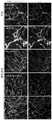

FIG. 1: a human vascular network is generated from human stem cells. a schematic representation of the protocol for differentiating human Embryonic Stem Cells (ESC) and human iPSC into vascular networks and free-floating organoids. The bottom panel shows representative morphology observed at the indicated differentiation step. b, c, immunofluorescence of endothelial cells expressing CD31 revealed the establishment of a complex, interconnected vascular network in the collagen I/matrigel matrix. d, CD31 based on confocal imaging+3D reconstruction of vascular network reconstruction Scale on 3 axes indicates. e, TNF α mediated activation of 3D endothelial network revealed by induced ICAM-1 expression.f-h is by CD31+Endothelial (green) and pericyte (red) coverage of the vascular network determined by endothelial and pericyte specific markers CNN1, PDGFR β, and SMA formation of the basement membrane is shown by collagen IV (colev) expression i, self-organizing human capillary organoids shown by immunofluorescence against collagen IV (colev) to visualize deposition of the basement membrane coating the endothelial vessels.

FIG. 2: mature, continuous human capillary blood vessel production. a, free floating organoids show a dense endothelial network closely covered by pericytes (CD31)+) Also shown is the 3D reconstruction of the entire free-floating organoid (top left panel). b, by targeting CD31+Immunofluorescence of endothelium and H&E staining shows endothelial lumen formation in free-floating vascular organoids. c, representative electron microscopy of free-floating vascular organoids. Note the generation of a cavitated continuous capillary-like structure with the appearance of a tight junction (white arrows) and basement membrane (black arrows). L, a cavity; e, endothelial cells. d, CD31+End cells (arrows) mark newly formed cells. Note the absence of ColIV at the site of angiogenesis+A base film. The magnification is shown in each figure.